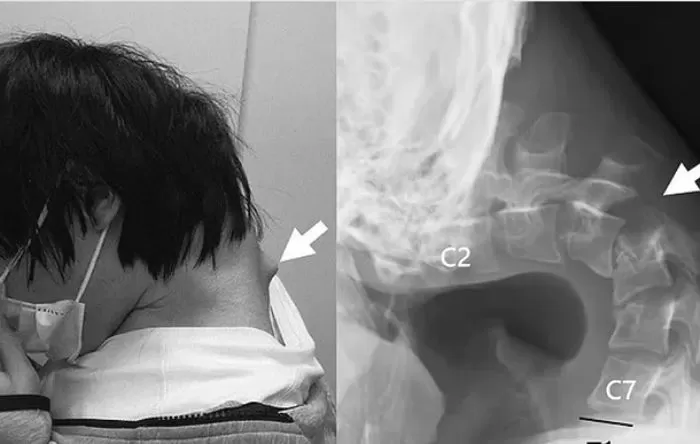

Các bác sĩ cho biết do bệnh nhân cúi đầu hàng giờ liền nhìn xuống điện thoại tạo nên một khối u lớn hình thành ở phía sau gáy. Chụp cắt lớp cho thấy đốt sống cổ của nam bệnh nhân bị biến dạng và trật khớp. Mô sẹo hình thành ở cột sống trên do bị "kéo giãn quá mức" trong thời gian dài.

Chàng trai bị u sau gáy do cúi đầu chơi điện thoại quá nhiều.

Nam bệnh nhân được chẩn đoán mắc "hội chứng cúi đầu". Đây là tình trạng bệnh lý hiếm gặp thường liên quan đến các bệnh thần kinh cơ bẩm sinh hoặc dị tật cột sống gây ra do giữ cổ cúi xuống trong thời gian dài.